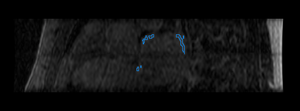

Finally, we show some preliminary results of our cardiac ablation scar segmentation obtained using this spatial prior knowledge and intensity thresholding. The figure on the right also shows an expert manual segmentation of the scar alongside our result.

Mdepa MDE scar segmentation.png Mdepa MDE scar seg 3D.png